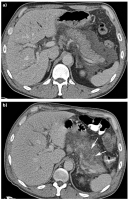

HCC

Abbildung 1: Hepatozelluläres Karzinom (HCC). (a) Die kontrastmittelverstärkte MDCT zeigt typischerweise in der arteriellen Phase eine verstärkte Kontrastmittelaufnahme des HCC (Pfeil) im rechten Leberlappen, neben der V. cava inferior. (b) In der venösen Phase zeigt sich ein rascher Wash-out, was typisch für ein HCC ist.